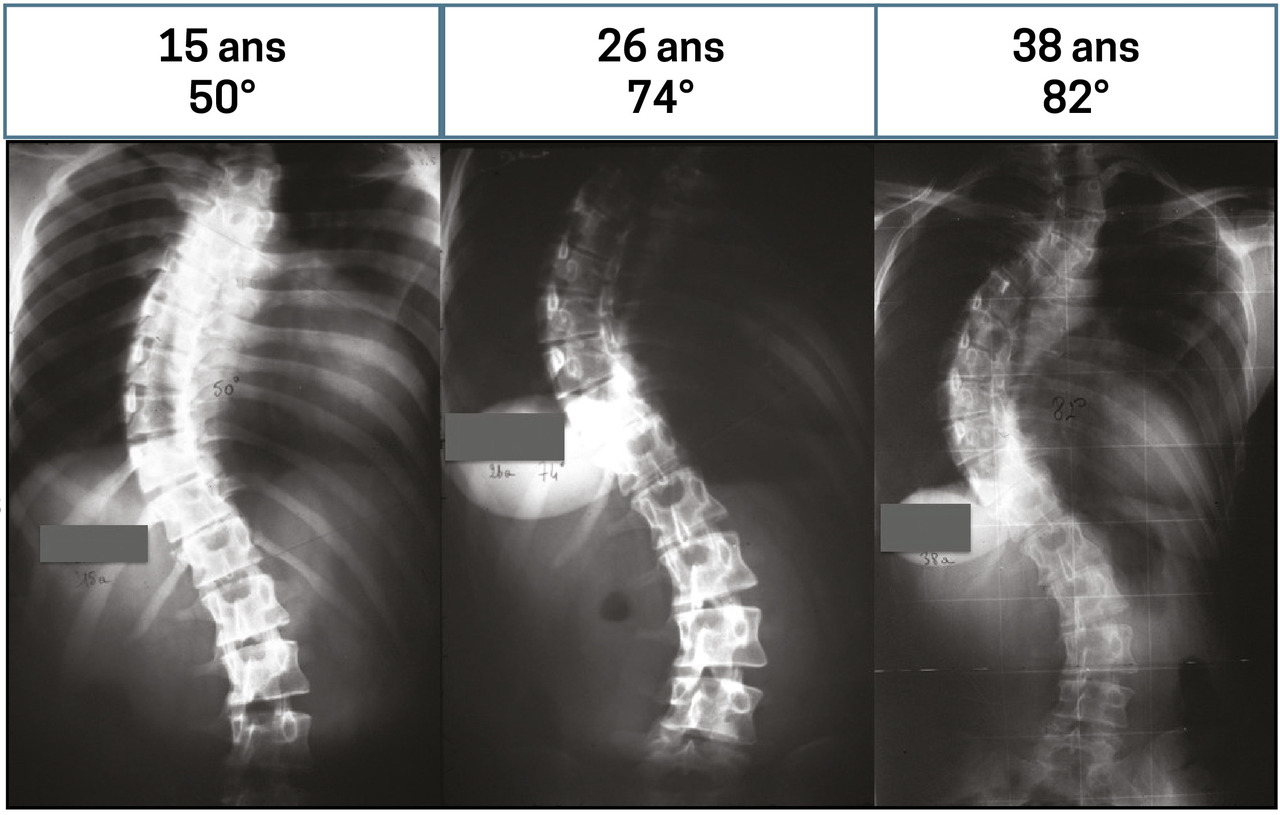

Pente d’aggravation souvent linéaire, en moyenne de 1° par an au-delà de 30° d’angle initial (fig. 1 ).

Rythme évolutif différent selon les individus : en moyenne, + 1° par an.

Aggravation inéluctable :

– soit continue, strictement linéaire ;

– soit lente, linéaire, suivie d’une accélération lors de la ménopause chez les femmes.

Une fois la greffe consolidée, plus de déformation (fig. 3 ) au fil des années, avec disparition des douleurs dans la zone opérée.

Une fois la greffe consolidée, plus de déformation (